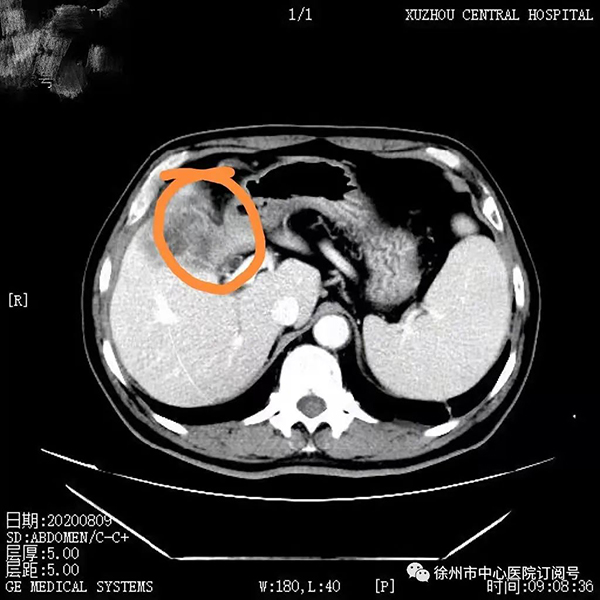

2020年8月腹部增強(qiáng)CT提示:膽囊壁增厚,考慮膽囊癌侵犯肝臟可能,膽囊結(jié)石合并膽囊炎癥,肝內(nèi)膽管輕度擴(kuò)張、積液。

2020年8月,董先生行第一次靶免治療,無特殊不良反應(yīng),后間隔21天行一次治療至第4療程;2020年10月腹部CT檢查見腫瘤較前縮小,病情持續(xù)好轉(zhuǎn);2021年4月進(jìn)行第9療程再次復(fù)查腹部CT顯示,此時(shí)腫瘤較第一次治療時(shí)已明顯縮小。